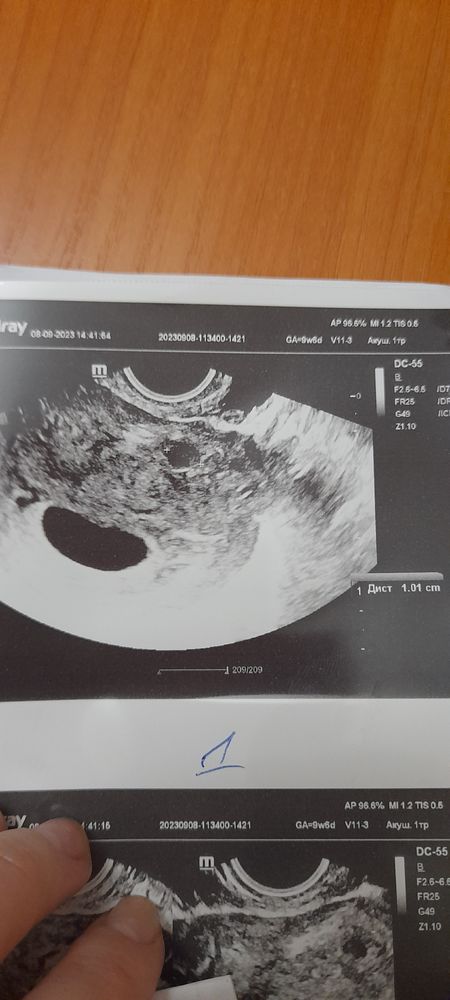

Здравствуйте. Делала узи три дня назад для подтверждения диагноза анэмбриония. Диагноз подтвердили( пустое плодное яйцо 26 мм), но ещё нашли миому 10 мм. Это уже седьмое по счету узи , последнее узи 10 дней назад, но ни на одном узи ничего не находили. И раньше тоже никогда такой диагноз не ставили. Откуда взялась эта миома? И могли ли её с чем-то другим перепутать? Ещё увидели варикозное расширение вен матки... но у меня обострение геморроя и я думаю, что это всё в комплексе, обострение ...